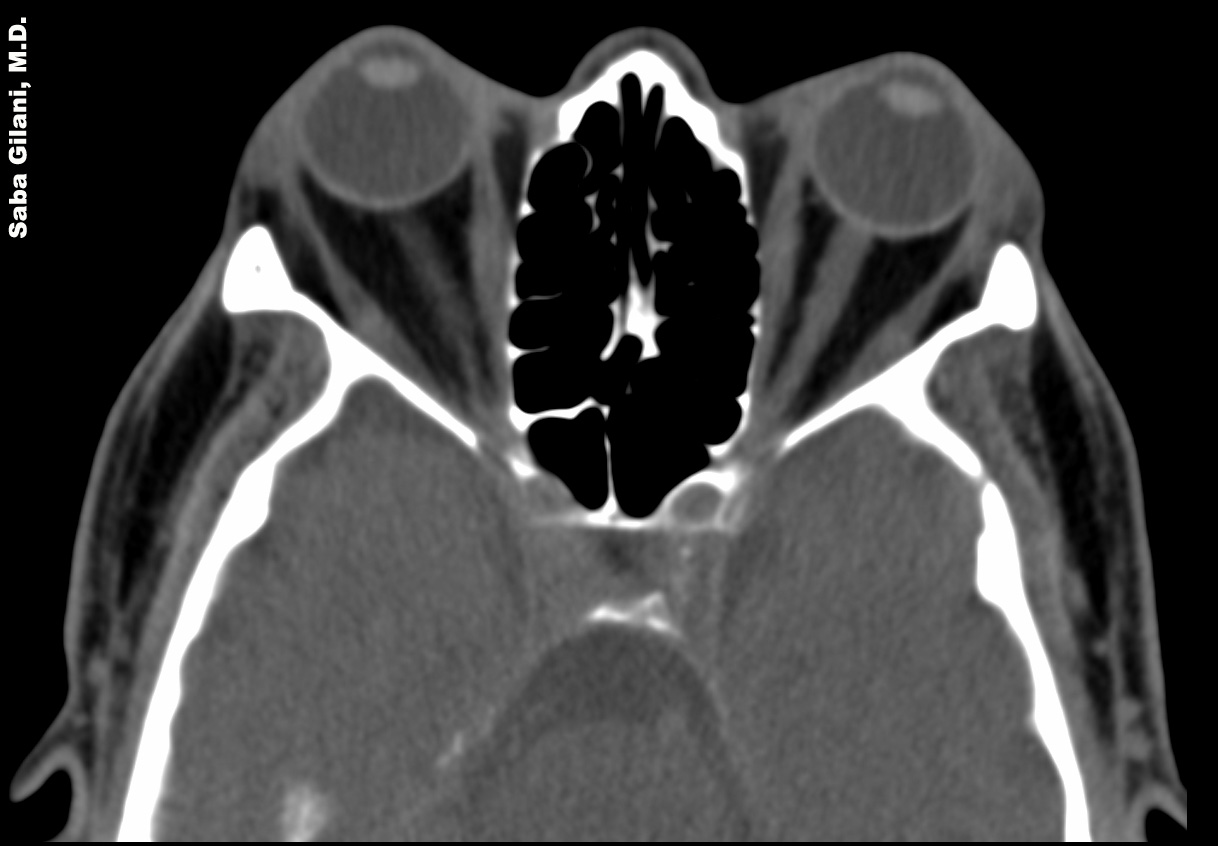

Endocrine Ophthalmopathy Ct . Ct remains the main imaging modality in graves' disease. Die diagnose erfolgt anhand von klinischen, neuroradiologischen. Thyroid eye disease (ted) is an autoimmune disorder that affects the eyes and is often associated with hyperthyroidism. Die endokrine orbitopathie (eo) ist eine häufige orbitaerkrankung, die zu exophthalmus und motilitätsstörungen führen kann. Overall, 84 of 91 patients (92.3%) demonstrated improvement or stabilization of ophthalmopathy. In this chapter, the reader will get acquainted with the clinical features, diagnosis and management of endocrine orbitopathy (eo). Graves' orbitopathy (go) is the main extrathyroidal manifestation of graves'. Ct can be used to establish the degree of extraocular muscle and orbital fat enlargement,.

In this chapter, the reader will get acquainted with the clinical features, diagnosis and management of endocrine orbitopathy (eo). Ct remains the main imaging modality in graves' disease. Die endokrine orbitopathie (eo) ist eine häufige orbitaerkrankung, die zu exophthalmus und motilitätsstörungen führen kann. Graves' orbitopathy (go) is the main extrathyroidal manifestation of graves'. Ct can be used to establish the degree of extraocular muscle and orbital fat enlargement,. Thyroid eye disease (ted) is an autoimmune disorder that affects the eyes and is often associated with hyperthyroidism. Die diagnose erfolgt anhand von klinischen, neuroradiologischen. Overall, 84 of 91 patients (92.3%) demonstrated improvement or stabilization of ophthalmopathy.

Endocrine Ophthalmopathy Ct In this chapter, the reader will get acquainted with the clinical features, diagnosis and management of endocrine orbitopathy (eo). Die diagnose erfolgt anhand von klinischen, neuroradiologischen. Overall, 84 of 91 patients (92.3%) demonstrated improvement or stabilization of ophthalmopathy. Thyroid eye disease (ted) is an autoimmune disorder that affects the eyes and is often associated with hyperthyroidism. Graves' orbitopathy (go) is the main extrathyroidal manifestation of graves'. Ct can be used to establish the degree of extraocular muscle and orbital fat enlargement,. In this chapter, the reader will get acquainted with the clinical features, diagnosis and management of endocrine orbitopathy (eo). Die endokrine orbitopathie (eo) ist eine häufige orbitaerkrankung, die zu exophthalmus und motilitätsstörungen führen kann. Ct remains the main imaging modality in graves' disease.